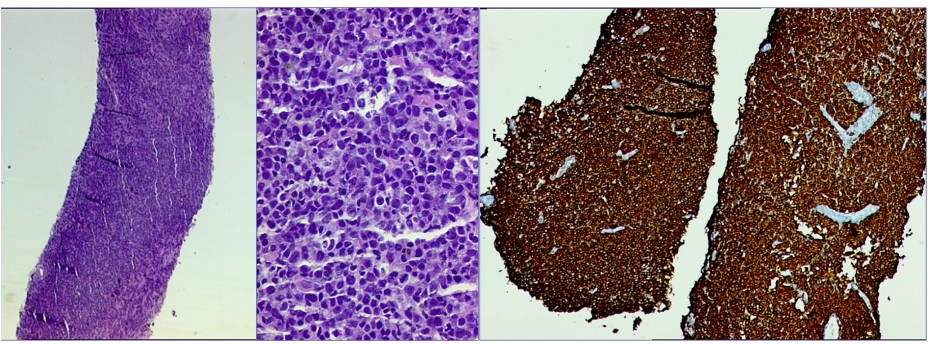

Mammography (Figure 1)revealed a large, round, well circumscribed, high density mass in upper outer quadrant and central region, measuring 7 x 6 cm. No suspicious calcification, architectural distortion, nipple retraction, skin or nipple-areolar thickening was seen. Associated was a large node measuring 11 x 9 cm noted in the left axillary region. Right breast and axilla were unremarkable. Correlation USG images were not available on Electronic Medical Record and PACS system, hence not available for reproduction here, however, as per the report, it appeared as a lobulated hypoechoic mass in left breast with necrotic changes, and internal vascularity in the solid component. Similar morphology additional left axillary mass was also seen. Imaging features highlighted the absence of spiculation, calcification, architectural distortion, irregular margins. The mass was categorized as BIRADS 4c, with a high probability of malignancy.Differentials on basis of mammography and USG were triple negative breast carcinoma, phyllodes tumor, cellular fibroepithelial lesion, organized abscess, lymphoma or metastases. CT was done to see disease extent which revealed a heterogeneously enhancing left breast mass (Fig 2a), large axillary and retropectoral adenopathy. No other adenopathy or abnormality seen. Biopsy from the breast lump was performed which showed Non-Hodgkin’s lymphoma of diffuse large B cell type, positive for CD20 and Mum1 which are markers of mature B cells. CSF study and Bone marrow aspiration were negative for involvement by disease. Diagnosis of primary breast lymphoma was made and planned for chemotherapy R-CEOP (rituximab, cyclophosphamide, etoposide, vincristine and prednisone) followed by IFRT (Involved field radiotherapy). Post 3 cycles of chemotherapy, FDG PET (Fig 2b and 3a) was done which showed significant reduction in size of breast mass and axillary node, breast mass then measuring 2 x 2cm with SUVmax of 7 while the axillary node measured 3.4 x 2.6 cm with SUV max of 3.7. Another repeat FDG PET Scan (Fig 2c and 3b)was done after completion of chemotherapy for further response assessment which showed no FDG uptake in left breast lesion suggesting complete metabolic response however size of the lesion appeared nearly stable, as compared to previous FDG PET (performed in the interim period of therapy). Patient has a 2-year disease free interval, and has not visited due to the Covid pandemic situation, but on telephonic follow up, is asymptomatic with good performance status. Figure 4: Low power (a), High power (b) and CD20 staining (c) from another case of primary breast lymphoma. These are representative images added here for teaching purpose. Figure 2a (10x power) shows diffuse infiltration by malignant cells. Figure 2b shows monomorphic round cells with apoptosis. Figure 2c staining positive for phenotype analysis for B cells. Representative USG image (Figure 5 and 6) of different patients with biopsy proven B cell lymphoma with different demographics. (Figure 5) USG of breast lump in a 56 year old woman shows hypoechoic, round mass, circumscribed margin with posterior acoustic enhancement mimicking a receptor negative carcinoma, mucinous carcinoma or fibroepithelial lesion. (Fig 6) Large mass in a 21 years old lady shows mixed echogenicity oval mass of parallel orientation, with well circumscribed margin and surrounding echogenic rim due to edema, mimicking a phylloides tumour, a fibroepithelial lesion or a malignant etiology.